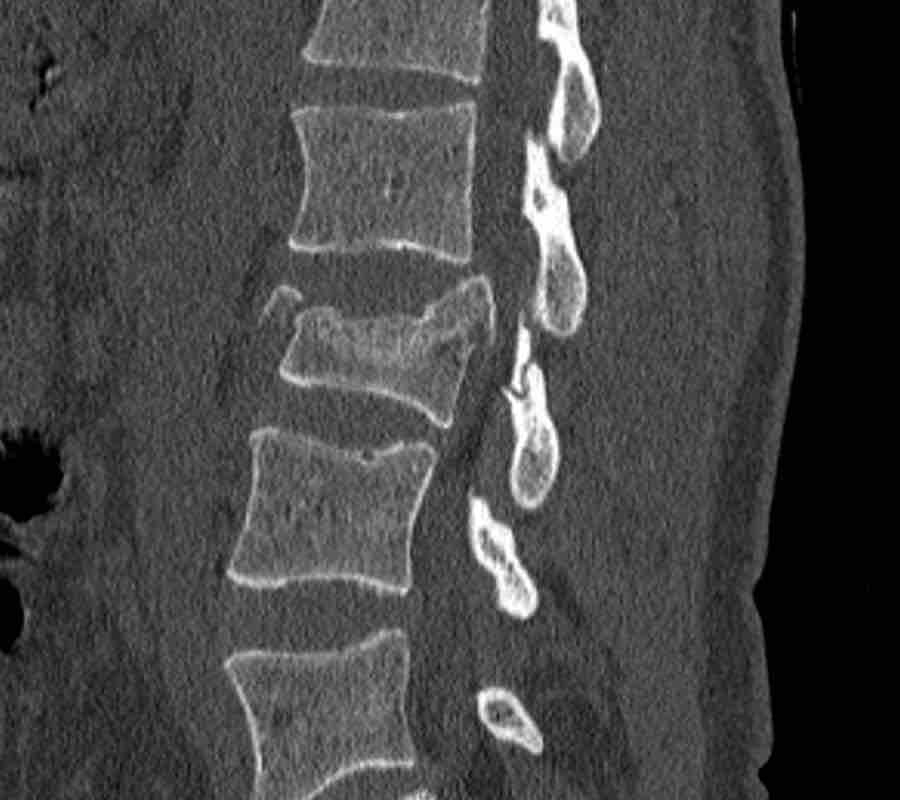

What is the type of the fracture of the vertebral body?

Findings:

- Fracture vertebral body with involvement of upper endplate (1 point), no posterior wall involvement

Conclusion

Injury type A1